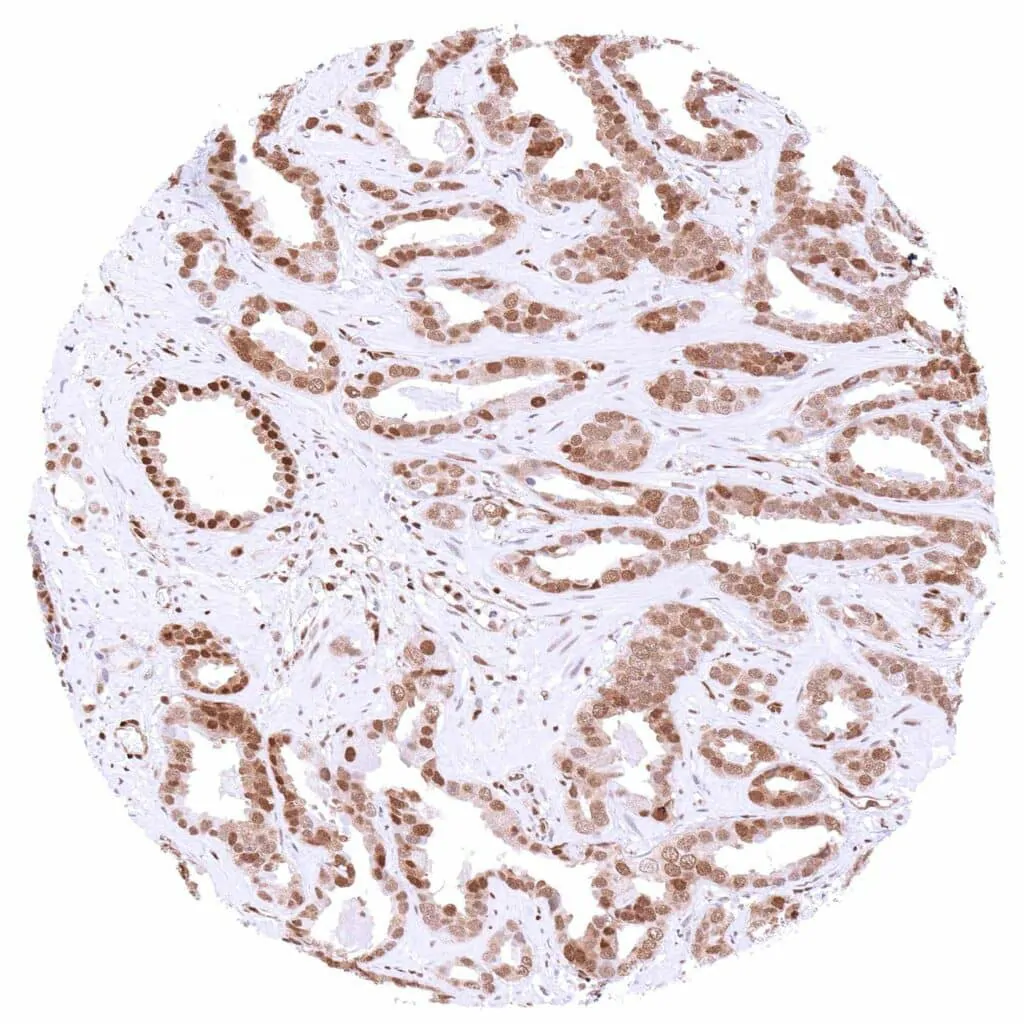

Kidney – Chromophobe renal cell carcinoma with distinct nuclear p27 staining of all tumor cells.